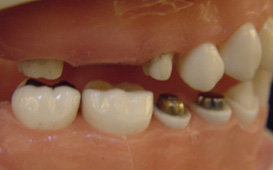

懸臂牙橋導致牙齒斷裂 ( 對側無牙 )